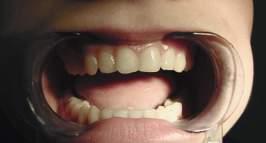

Długotrwała aktywność parafunkcjonalna nie pozostaje obojętna również dla zębów. Do najczęstszych wewnątrzustnych objawów bruksizmu zaliczamy: ubytki klinowe, tarczki wytarcia, ubytki w brzegach siecznych, recesje dziąsła (patrz ryc. 1.11a–c), pęknięcia szkliwa.